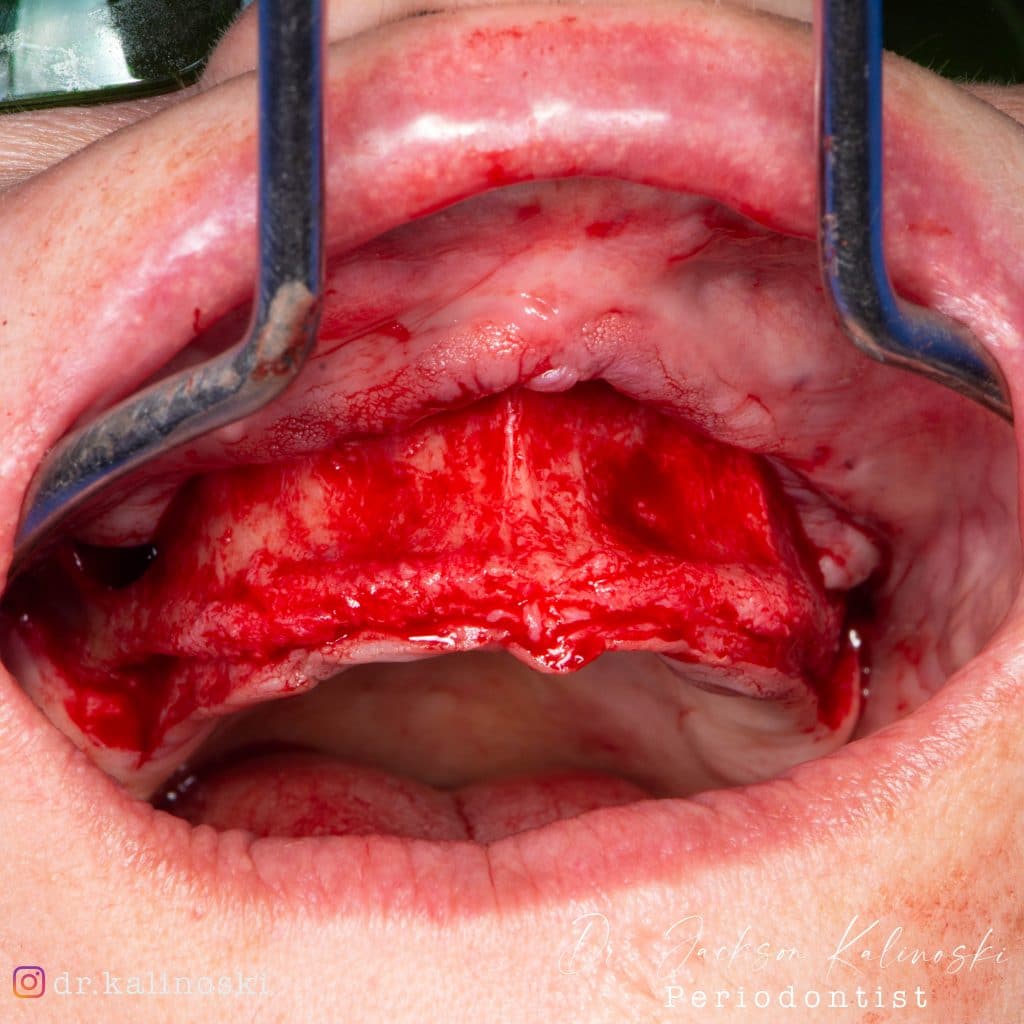

Olá colegas, aqui está um caso didático de reconstrução óssea total da maxila, levantamento do seio maxilar bilateral e bloqueio espesso com aplicação do conceito de PRF e Biotensigrity.

SEM tela, SEM parafusos, SEM membranas de colágeno. Substitua apenas osso aloplástico e sangue.